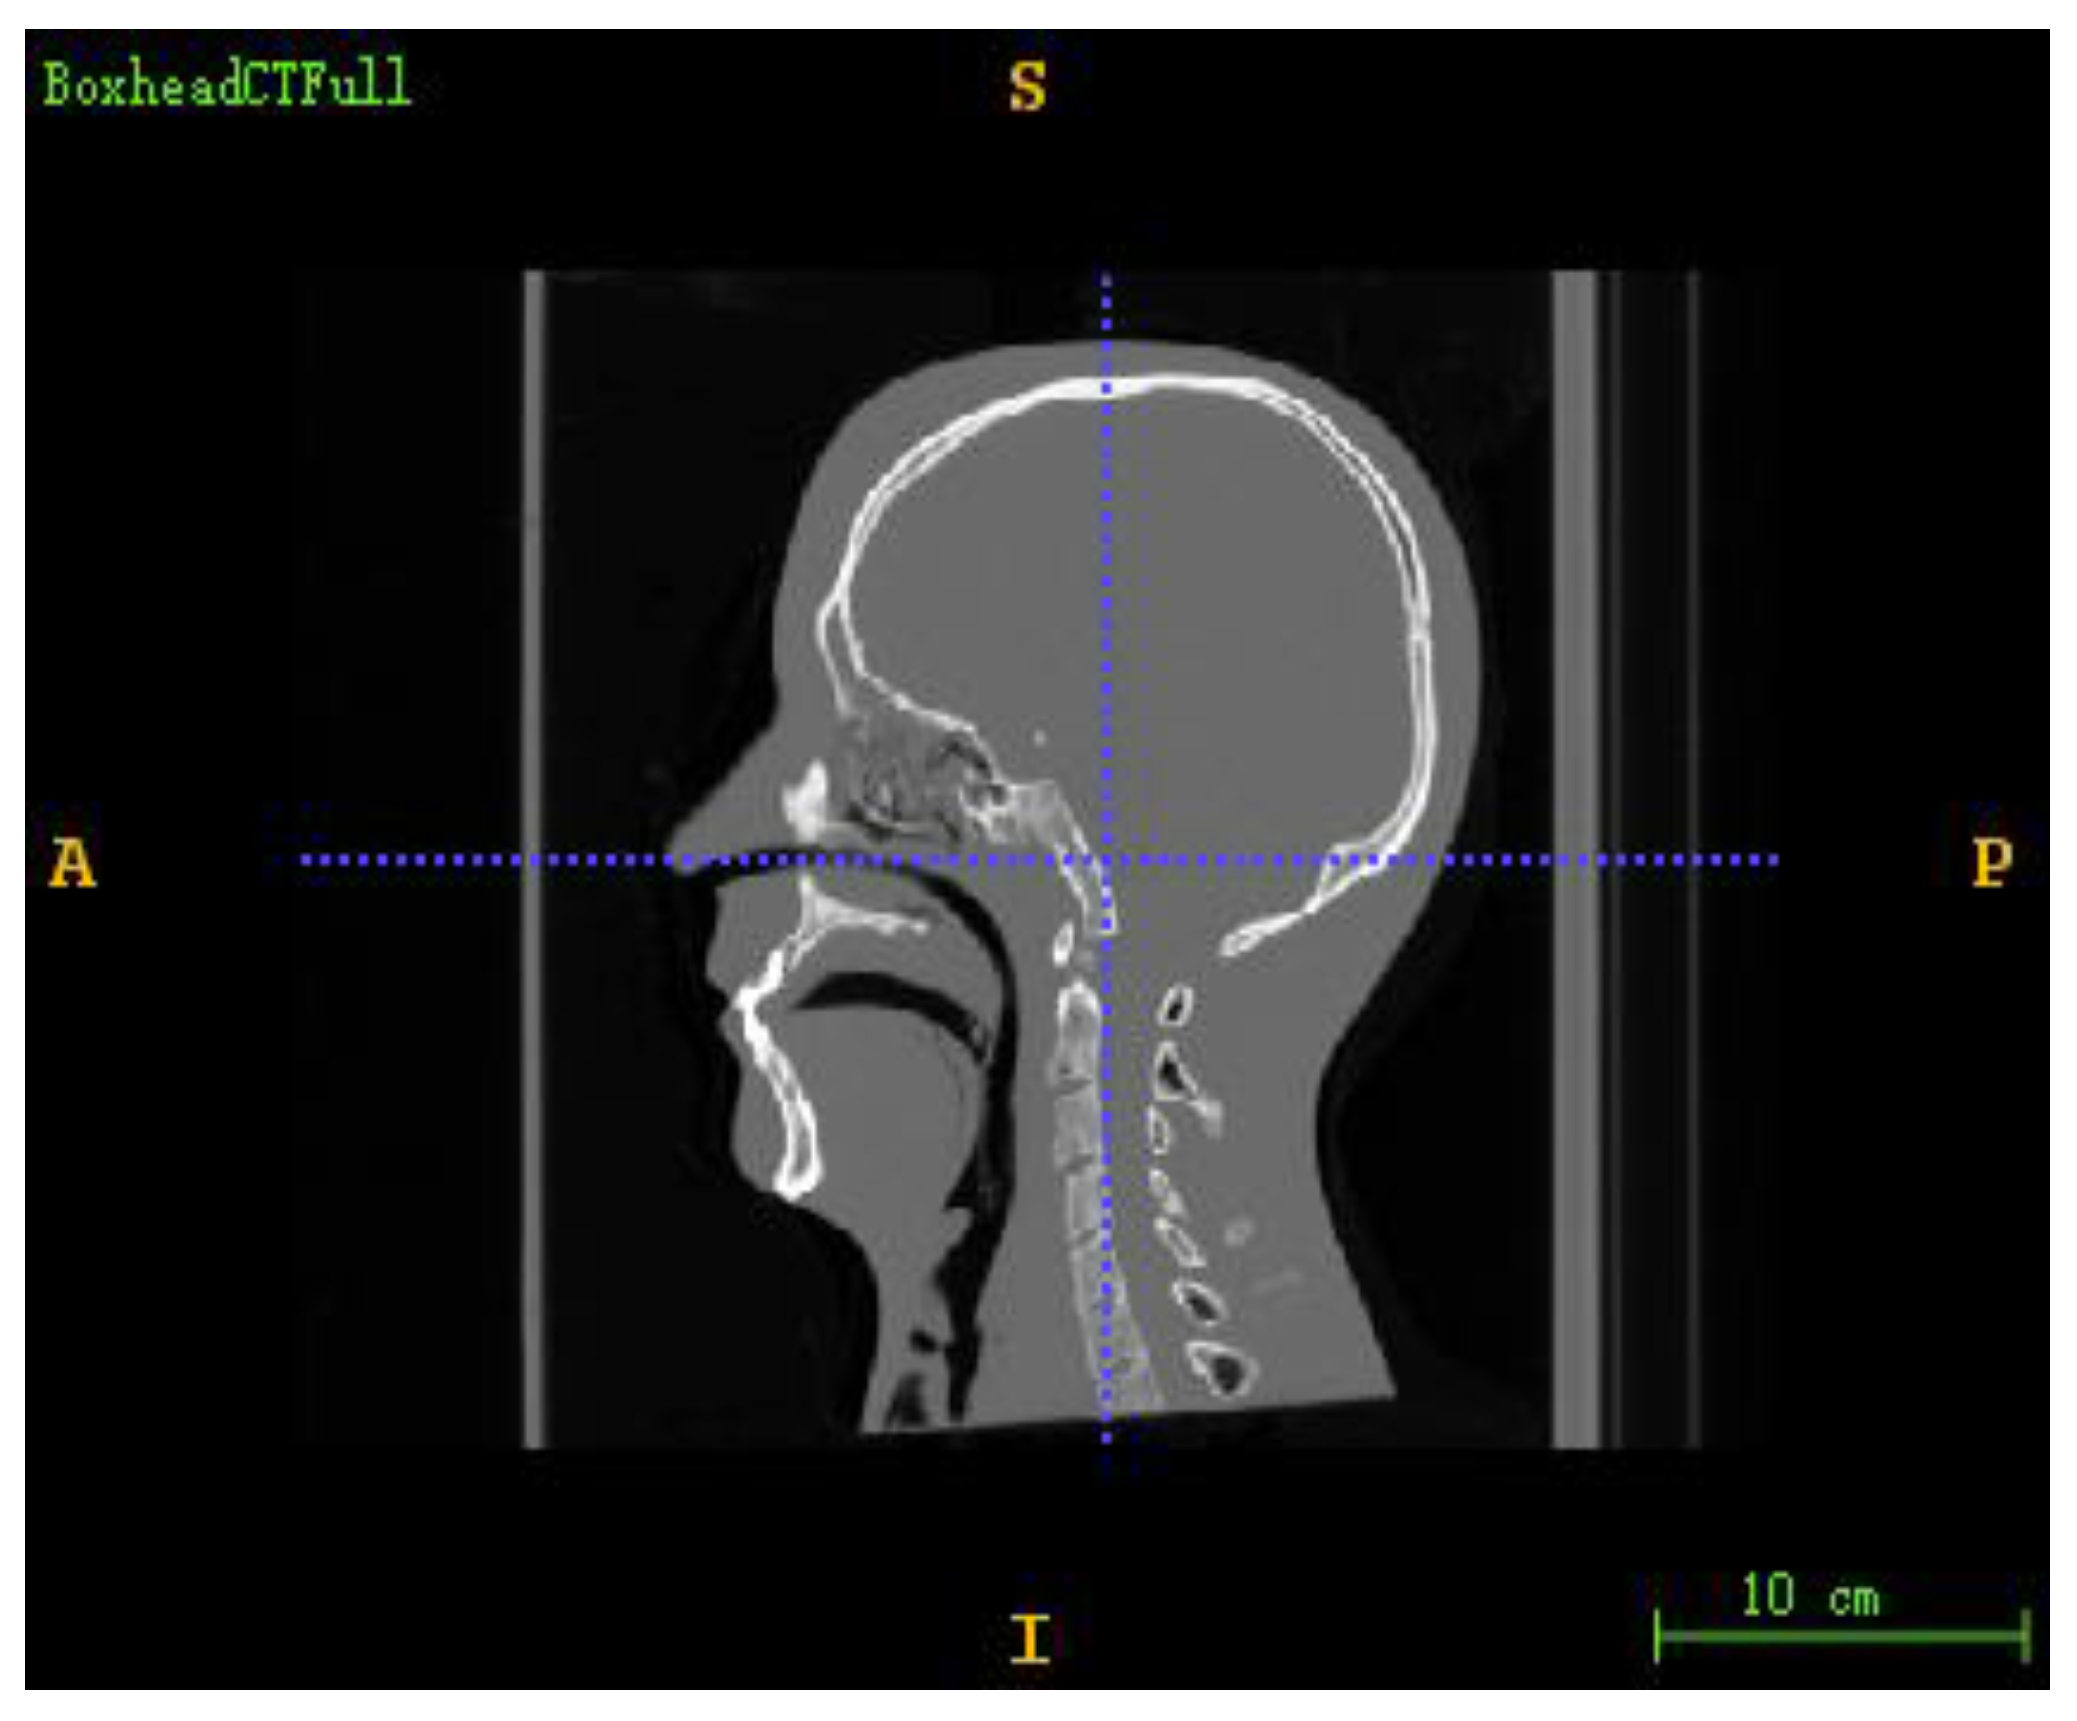

The DICOM sequence obtained from the human brain model’s CT scan was used as a 3D floating image in the registration experiment. In addition, the digitally reconstructed radiograph (DRR) generated by projection rendering under specific CT parameters was used as a 2D reference image to simulate a real X-ray image. The size of the CT image was 512 × 512 × 283, the voxel spacing was 0.7813 × 0.7813 × 1.0, and the unit was mm. The projected image size was 512 × 512, the pixel spacing was 0.5 × 0.5, and the unit was mm. The 3D screenshot of the CT image is shown in Figure 1, and the 3D model rendered by the CT image is shown in Figure 2.

Figure 1. Three dimensional CT image of the brain model.